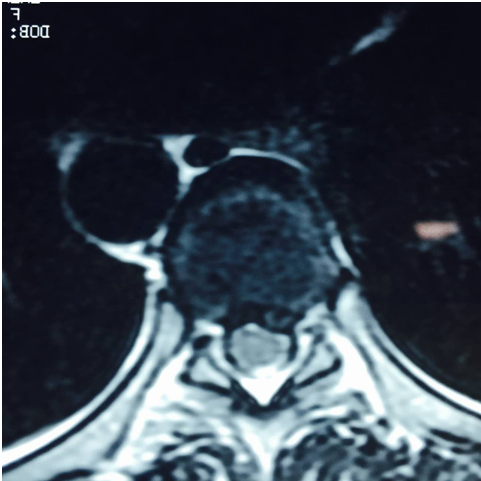

术前磁共振

(术前磁共振